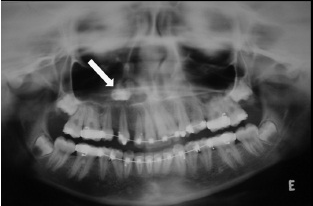

3. What condition can be seen in the following X ray?